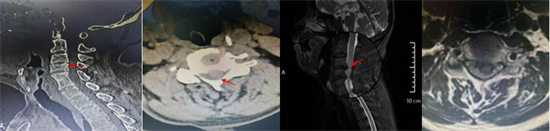

術(shù)前影像資料顯示C3/C4椎間盤突出、極重度頸椎椎管狹窄、C5/6椎體融合

患者李某,70歲,因“四肢乏力、行走不穩(wěn)1年,加重1個(gè)月”入住衡南縣人民醫(yī)院骨科二區(qū),入院檢查診斷為:脊髓型頸椎病、頸椎椎管狹窄癥(C3/C4極重度)、慢性不完全性四肢癱。其中C3/4節(jié)段椎管占位率超過50%以上,脊髓受壓極其嚴(yán)重,若病情繼續(xù)進(jìn)展,可能導(dǎo)致高位截癱甚至呼吸衰竭,危及生命。且李某還存在C5、6節(jié)段先天性融合,短頸畸形,進(jìn)一步增加了術(shù)中暴露和置釘?shù)碾y度,對(duì)主刀醫(yī)生的經(jīng)驗(yàn)、技術(shù)及團(tuán)隊(duì)配合要求極高。

術(shù)后復(fù)查顯示內(nèi)固定位置良好、椎管減壓充分,患者自覺癥狀明顯緩解

為確保手術(shù)成功,骨科二區(qū)專家團(tuán)隊(duì)與湘雅三醫(yī)院苗驚雷教授緊密協(xié)作,在麻醉科和手術(shù)室的配合下,成功為患者實(shí)施頸前路椎間盤切除術(shù)+椎管擴(kuò)大減壓術(shù)+植骨融合內(nèi)固定術(shù),患者術(shù)后即感四肢肌力明顯改善,目前恢復(fù)良好,已順利出院。